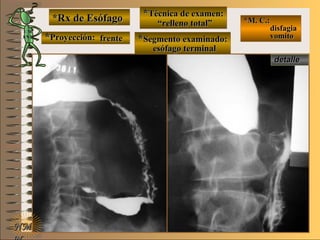

*Rx de Esófago*Rx de Esófago

**Proyección:Proyección:

**Técnica de examen:Técnica de examen:

**Segmento examinado:Segmento examinado:

*M. C.:*M. C.:

disfagiadisfagia

vomitovomito

NMNM

““relleno total”relleno total”

esófago terminalesófago terminal

A-A-El examen es normal o patológico?El examen es normal o patológico?

Examen patológico de esófago toráxico conExamen patológico de esófago toráxico con

técnica de relleno total en proyección de frentetécnica de relleno total en proyección de frente

B-B-La patología es congénita o adquirida?La patología es congénita o adquirida?

Patología adquiridaPatología adquirida

C-C- Dicha patología es orgánica, funcional o mixta?Dicha patología es orgánica, funcional o mixta?

Patología adquirida orgánicaPatología adquirida orgánica

D-D-La misma es neoplásica o no neoplásica?La misma es neoplásica o no neoplásica?

Patología adquirida orgánica no neoplásicaPatología adquirida orgánica no neoplásica

E-E-Puede describir la o las imágenes patológicas?Puede describir la o las imágenes patológicas?

Se identifica una alteración de tamaño y longitudSe identifica una alteración de tamaño y longitud

de esófago toráxico (dolico-mega) asociado a unade esófago toráxico (dolico-mega) asociado a una

estenosis orgánica céntrica y regular en esófagoestenosis orgánica céntrica y regular en esófago

distal, compatible con acalasia (destrucción dedistal, compatible con acalasia (destrucción de

plexos nerviosos de Meisner y Auebach)plexos nerviosos de Meisner y Auebach)